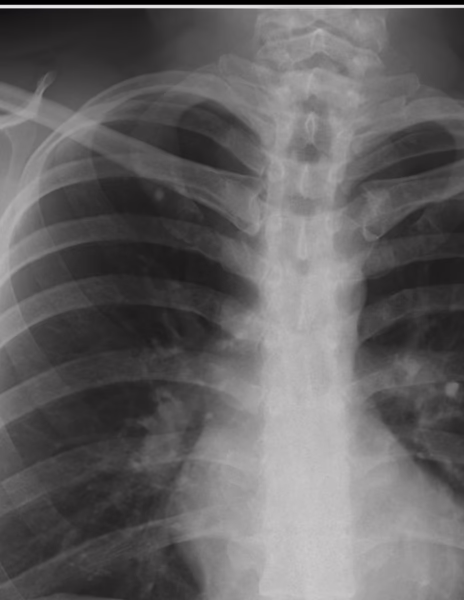

Se identifican los tejidos blandos y oseos de densidad homogénea.

El cardiomediastino muestra un índice cardiotorácico en limites normales, la aorta asi como el flujo vascular pulmonar se considera normal.

Los hemidiafragmas de apariencia normal, los ángulos cardiofrenicos y costodiafragmaticos se observan libres.